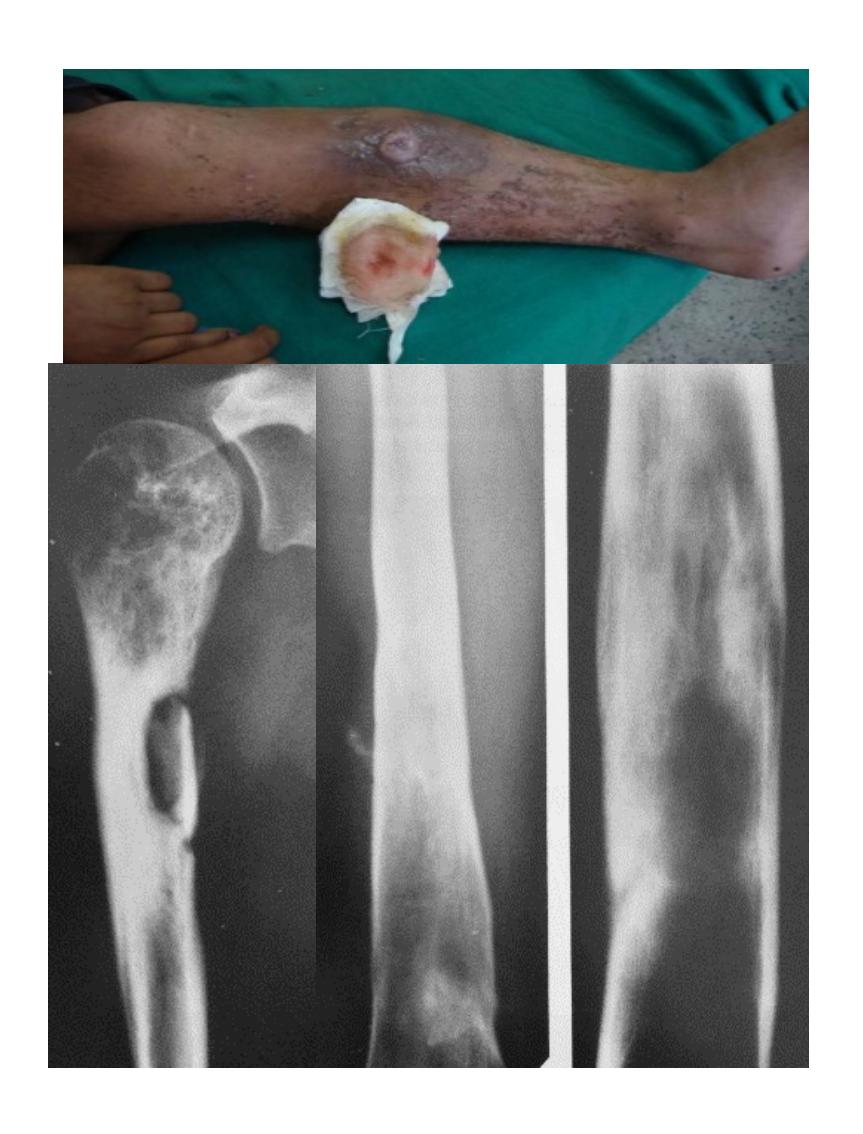

| Compartment Syndrome | Increased pressure within a closed fascial compartment, leading to reduced tissue perfusion, hypoxia, and irreversible muscle and nerve damage. Causes: Fractures (especially tibia/forearm), severe soft tissue trauma, arterial injury, burns, tight casts/dressings, post-ischemic reperfusion swelling, IV fluid extravasation, and bleeding disorders (e.g., hemophilia). High-Risk Notes: Pain may be absent in altered consciousness, children (monitor analgesia response), polytrauma, sedated/epidural cases, or concomitant nerve damage. Open fractures do not always decompress pressure. Gross/Clinical: -tense, shiny leg swelling with blisters in compartment syndrome.Imaging: - Intraoperative fasciotomy | History/Symptoms: Pain out of proportion to the injury (e.g., a “bursting” sensation), which is not relieved by analgesia. Clinical Features (The 5 P’s): - Pain with passive stretch (early, key sign; e.g., ankle dorsiflexion for leg, wrist for forearm). - Paresthesia (early). - Palpable tense swelling (shiny skin, blisters: clear=mild, serosanguinous=severe, bloody=worst; dusky/pallor skin). - Pallor, Paralysis, Pulselessness (late, ominous signs; pulses often palpable until late). Investigations: Primarily a clinical diagnosis (high suspicion key). Compartment pressure measurement can confirm: absolute pressure >30 mmHg or Delta Pressure (Diastolic BP - Compartment P) ≤ 25 mmHg. | Initial: ABCs, supplemental oxygen. Remove all circumferential dressings, casts (bivalve to skin), and splints. Elevate the limb to heart level (not above; higher reduces inflow). Correct any hypotension. Surgical: Urgent Fasciotomy if no response within 1h or confirmed pressure (prophylactic in high-risk like major osteotomy). Release all compartments/skin with long incisions; debride necrotic muscle via 4C’s (early: pink/red, soft, contracts/bleeds on pinch; late: dark, firm, no response); preserve neurovascular. Wound open (bulky dressing/splint, VAC, or boot-lace gradual closure); repeated inspections x48h; coverage in 3-5 days (skin graft usual; flap if nerves/vessels/bone exposed). | Cellulitis, Deep Vein Thrombosis (DVT), Arterial occlusion, Severe soft tissue injury without compartment syndrome; equivocal cases in polytrauma. | Complications: Volkmann’s ischemic contracture (permanent deformity, weakness, sensory loss, chronic pain). Contraindications (Fasciotomy): Confirmed >48h (irreversible damage, high infection risk from dead tissue); crush injuries with already necrotic muscle. |

| Open Fracture | A fracture with a breach in the overlying skin and soft tissues, creating communication with the external environment. All open fractures are considered contaminated (even small punctures; aka compound fracture). Causes: Can result from high-energy trauma (RTAs, falls, firearms; signs: degloving, crush syndrome, bone loss, segmental) or low-energy trauma. Contamination risk higher with farm/soil injuries, bites, delayed presentation (>12h), fecal/oral/soil/water exposure. Mechanism: Low/high velocity missiles (cavitation >300 m/s); in-out (cleaner) vs. out-in (dirtier). Gross/Clinical: ![]() | History: Mechanism of injury (energy, time, place, type/impact method), consciousness, wound size/bleeding amount, other injuries (often missed), tetanus status. Assessment: ATLS protocol (ABCDE) first (treat patient, not fracture; exclude shock/brain injury, monitor vitals; viscera exam: ribs=lungs/liver/spleen, pelvis=bladder/urethra). Examine wound (look/feel/move carefully post-splint), check distal neurovascular status, compartment syndrome. Photograph/remove gross contamination; cover with saline dressing. Classification (Gustilo-Anderson): - Type I: <1 cm wound, clean, minimal soft tissue. - Type II: >1 cm wound, moderate soft tissue (no stripping). - Type IIIA: Extensive soft tissue damage, but adequate bone coverage. - Type IIIB: Extensive soft tissue loss with periosteal stripping; bone exposed, requires flap coverage. - Type IIIC: Any open fracture with an arterial injury requiring repair. | Initial (ER): ATLS first. Cover wound with sterile saline-soaked dressing, splint limb, IV fluids (request blood if needed); traction if no distal pulse/deformity. Prophylaxis: Tetanus prophylaxis/serum and broad-spectrum IV antibiotics immediately (culture tissue/blood); clean major contamination. Surgical: Urgent debridement/irrigation within 6-12h (“Dilution is the solution to pollution”; pulse-irrigate 3-6-9L saline; excise non-viable tissue/foreign material, trim skin edges, remove dead muscle/detached bone, preserve N/V). Stabilization: external fixator (preferred severe; replace with cast post-infection); internal if clean/minimal. Wound closure delayed (primary if small/clean; secondary if contaminated/large). Early soft tissue cover. | The diagnosis is typically obvious. Key: Classify severity; identify associated injuries like compartment syndrome, vascular damage, or high-energy signs (e.g., crush). Differentials for contamination: Primary (field debris) vs. secondary (post-fixation if poor debridement). | Complications: Infection (cellulitis, osteomyelitis, chronic with sequestra/drainage, gas gangrene), tetanus; higher with delay/exposure/bites. - embolisms fat, thrombi others.. Case Insight: Unconscious patient (e.g., open tibia post-RTA): ABCDE/cervical collar, distal pulses/traction, admit for debridement; ankle fall: Splint post-ABC, assess neurovascular. |